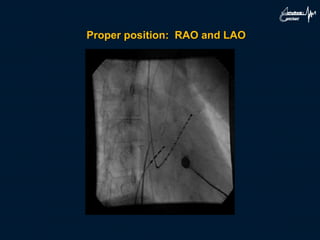

Proper position: RAO and LAO

Heart 2009;95:85–92. doi:10.1136/hrt.2007.135939

5. Confirm correct position in RAO (ant-post: needle

should be post to pigtail in aorta parallel with spine.

• With the x ray positioned at 30 left anterior oblique

(LAO) the sheath and catheter are rotated so that both

are pointing approximately to the 4–5 o’clock position.

6. Confirm in LAO: needle should be directed posterior.